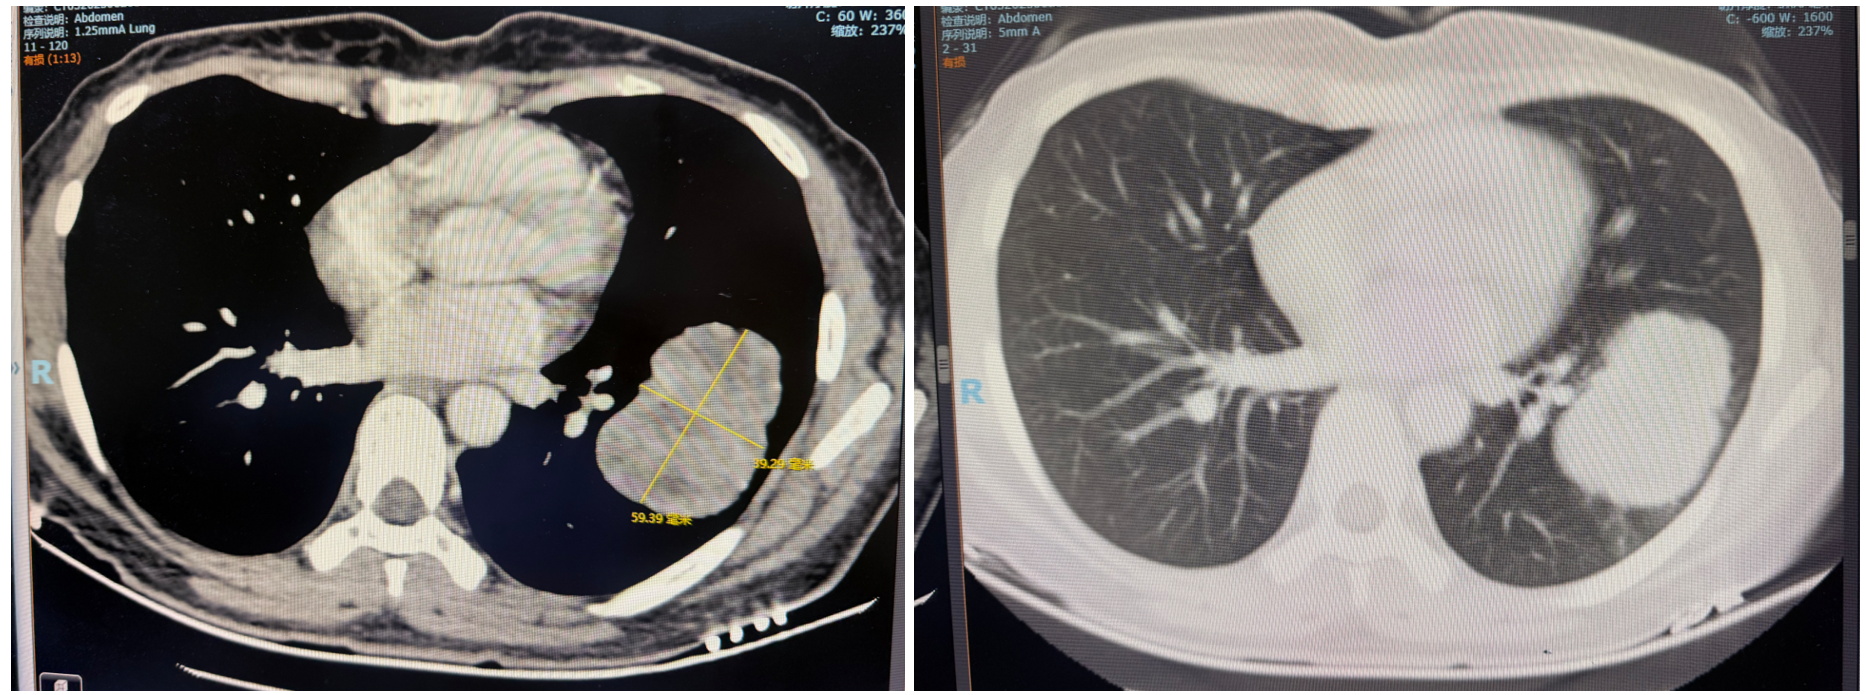

• 2025年8月(新辅助2周期后)复查肺CT:左肺下叶占位较前明显缩小(病灶直径缩小至16.52mm)。

图2 2025年8月CT图像

• 2025年9月(新辅助3周期后)复查肺CT:左肺下叶占位进一步缩小,疗效评价达到部分缓解(PR)。

图3 2025年9月CT图像